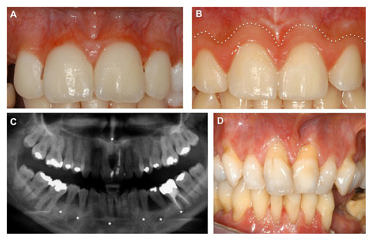

13- Periodontal EDS (pEDS): C1R veya C1S’deki heterozigot mutasyonlarından kaynaklanır. Periodontal EDS (pEDS), Ehlers-Danlos Sendromu nun en nadir formudur. Periodontal EDS (pEDS), otozomal dominant modelde kalıtılır. Kesin teşhis için genetik test gereklidir. [5]

Yaygın semptomlar:

- Erken başlangıçlı periodontitis (bu durum 30 yaşından önce diş kaybına neden olabilir)

- Kısa boy

- Ciltte oluşan koyu lekeler (hiperpigmente)

- Atrofik izler

- Aşırı uzayabilir cilt

- Aşırı esnek eklemler

- Dişlerden normalden daha küçük (mikrodonti)

- Diş etlerinin aşırı büyümesi

- Kalıcı dişlerin gelişmemesi